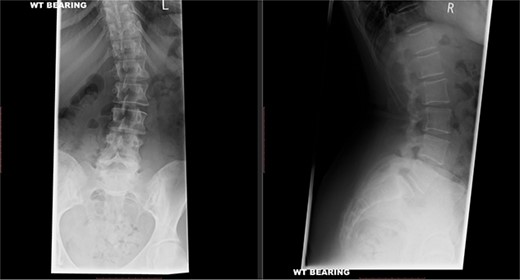

A repeat MRI scan (Fig. 2) performed in December 2016 did not show any interval changes as compared to the scan performed in February 2016. The patient presented elsewhere and was recommended for spinal fusion surgery. A posterior pedicle screw instrumentation with rods and a posterior interbody cage procedure was performed elsewhere in January 2017.

Preoperative MRI of the lumbar spine performed in December 2016. The MRI shows no neurological compression.